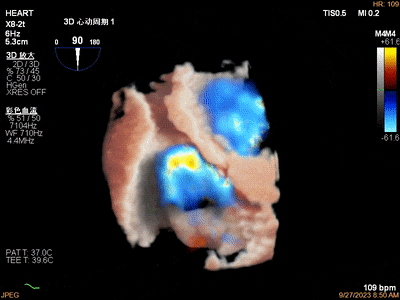

1、心脏自体瓣膜病变:如感染性心内膜炎、瓣膜返流及狭窄的病因诊断、瓣膜脱垂的病因及定位诊断等。

感染性心内膜炎二尖瓣前叶穿孔三维图